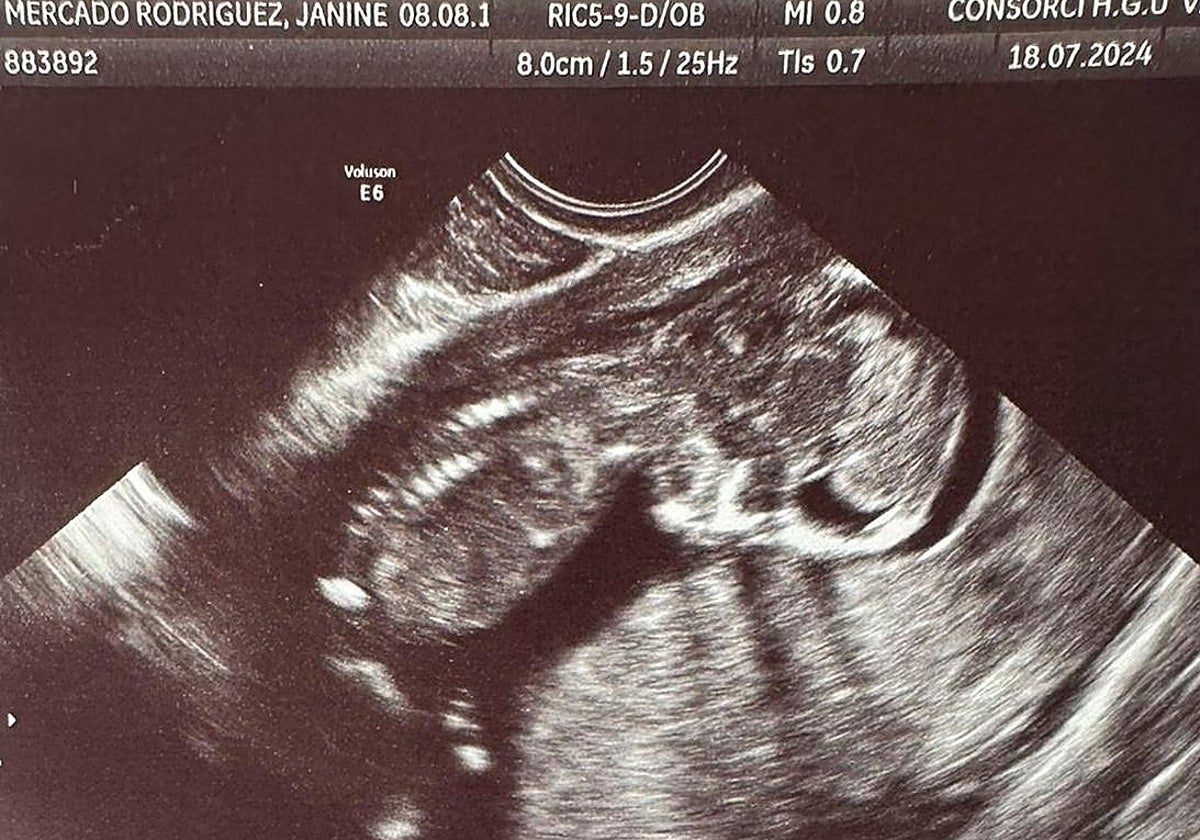

La cuna ya estaba montada y muchos de los objetos para Escarlett, adquiridos. Por si la niña en camino se adelantaba. «El lunes fue a buscar el carro para la bebé y, el miercoles, tenía la última ecografía». Como tantas otras veces, fue de Godelleta a Ribarroja, cogió el camión en el polígono, e hizo su trabajo. Ya por la tarde, hizo el recorrido a la inversa. Y fue ya en coche, de vuelta a casa, cuando el desbordamiento del Poyo le sorprendió en la rotonda de Ribarroja.